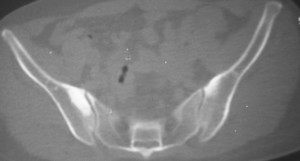

标题: CT7246: F,30岁,下腰痛,同事的片子,请老师们看看,初 [打印本页]

标题: CT7246: F,30岁,下腰痛,同事的片子,请老师们看看,初

典型的双侧骶髂关节致密性骨炎.

何谓髂骨致密性骨炎?髂骨致密性骨炎是发生于髂骨耳状关节部分的骨质密度增高性疾病。病因迄今不明,可能与妊娠、机械性劳损、病灶性炎症有关。本病好发于20~35岁的育龄妇女,偶见男性。

髂骨致密性骨炎的临床表现与体征:腰骶部疼痛,多呈慢性、间歇性酸痛、隐痛,可向一侧或双侧臀部及大腿后侧扩散,但不沿坐骨神经方向放射,步行、站立、负重及劳累后加重,咳嗽、打喷嚏不能使疼痛明显加重,休息后症状减轻。患者腰骶角加大,局部有压痛和肌紧张,骨盆分离和挤压试验阳性,“4”字试验阳性,化验检查多在正常范围内。x线检查,骶髂关节间隙整齐清晰,靠近骶髂关节面中的髂骨耳状关节部分骨质密度增高,呈均匀浓白边缘清晰的骨质致密带,骨小梁消失,无骨质破坏。本病应注意与早期强直性脊柱炎、骶髂关节结核相鉴别。